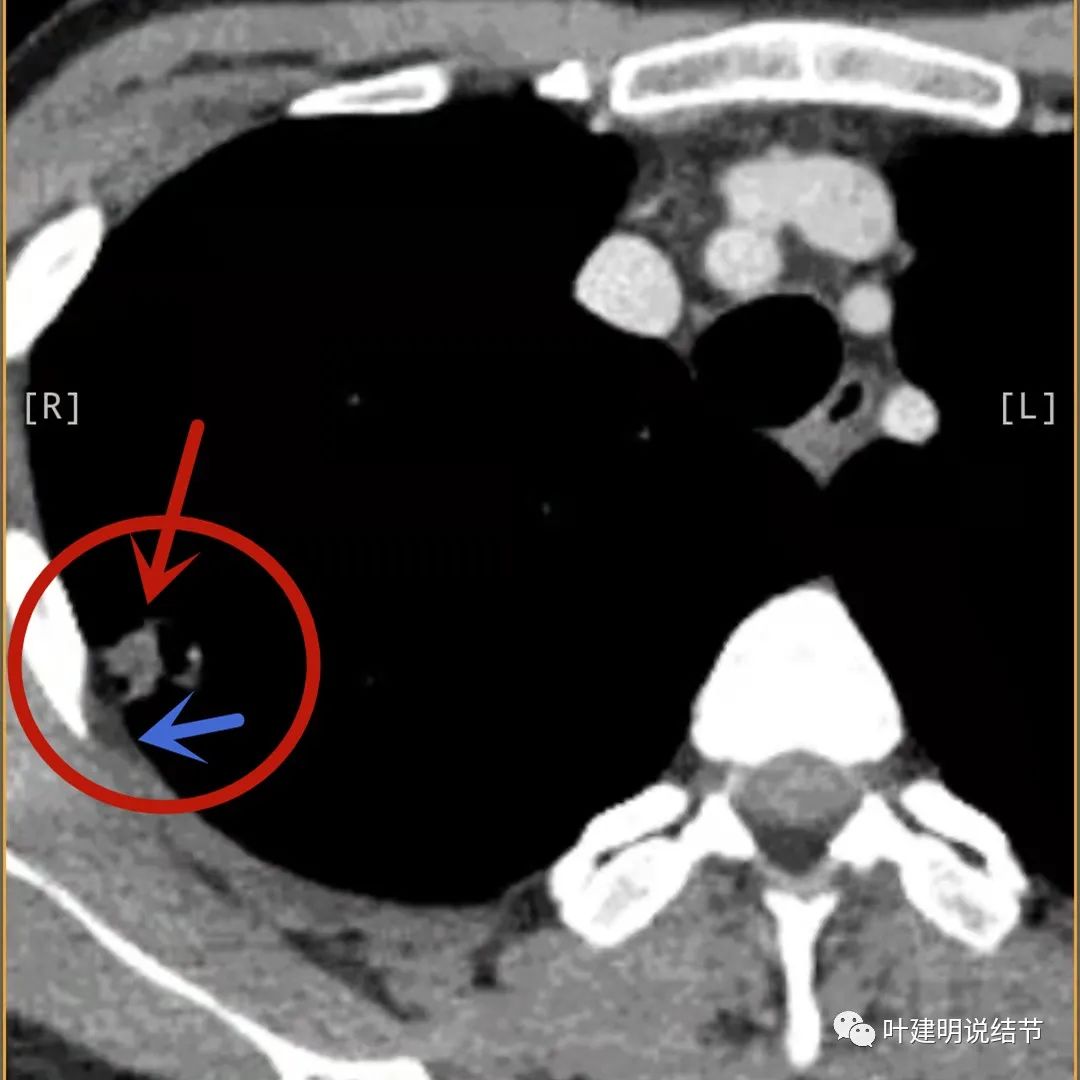

病灶有空洞(黄色箭头),主病灶边上见条索状高密度影(细红色箭头),邻近胸膜有粘连(蓝色箭头)